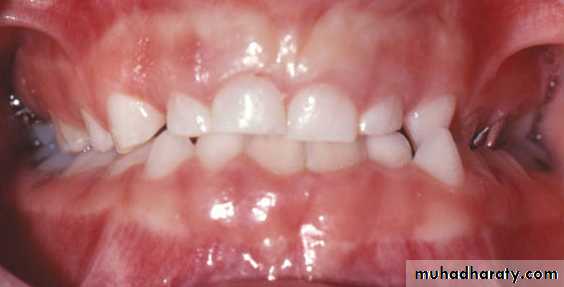

Marked bilateral narrowing produce no interference and the patient will have bilateral crossbite in centric relation.Less frequently unilateral posterior crossbite is caused by true unilateral narrowing of the upper arch, the patient has crossbite in centric relation and centric occlusion.

Bilateral crossbite

True unilateral crossbite